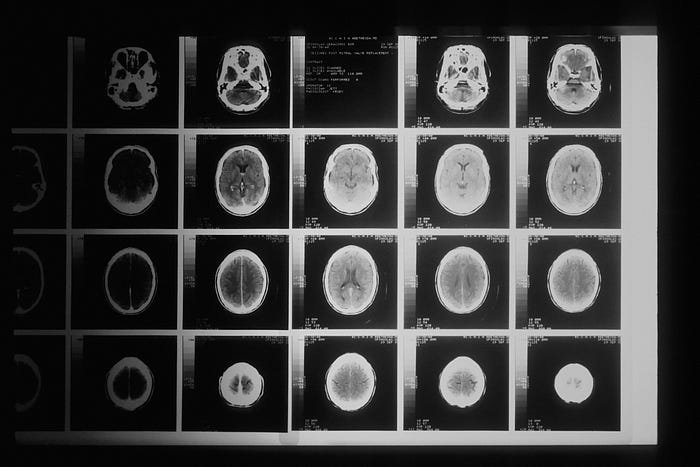

The dataset comes from Kaggle [5], which contains a database of 3206 brain MRI images. The images are separated into four categories: no tumor, glioma tumor, meningioma tumor, and pituitary tumor. Figure 2 shows a sample image for each category.